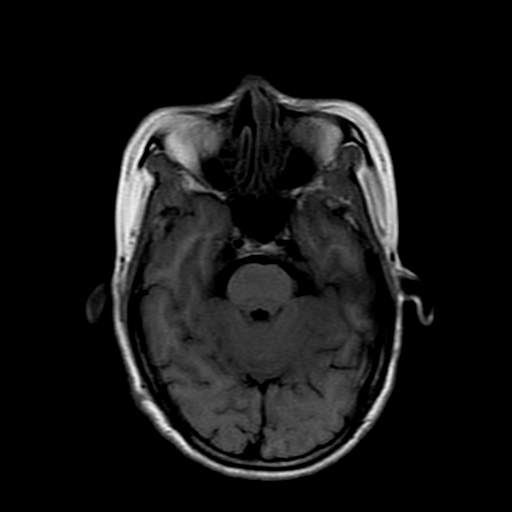

女性,47岁。mri号03027,外伤致头痛9天,抽搐一天,原无类似病史。

dwi及矢状位无明显异常,所以没发。

双侧海马的信号都有异常。

双侧海马硬化!

颞叶前部萎缩,海马萎缩,t2wi海马高信号,支持海马硬化。

双侧海马硬化.

双侧海马区t1低,t2高信号。为什么都考虑硬化?发病原因?鉴别诊断:炎症,梗塞等能一下子除外吗?